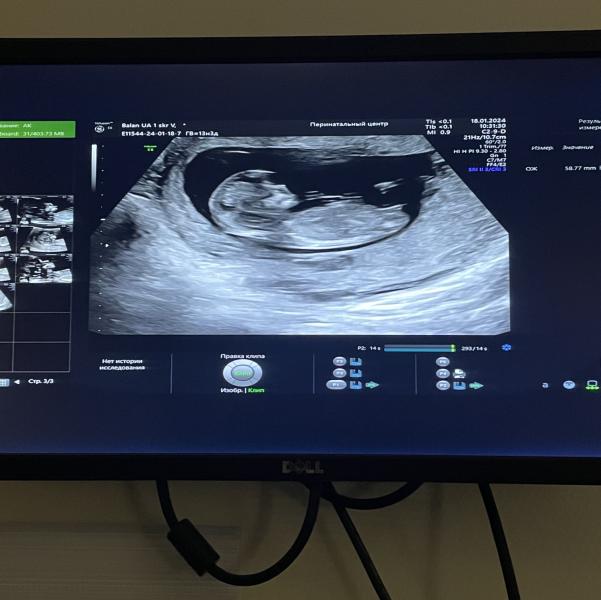

Ну вот и прошёл первый скрининг-всё хорошо🥹

Срок поставили 12,3 .

Сказали больше похож на девочку, ждем второй скрининг что бы точно узнать (14.03)

И вот с дочкой было 157, с сыном 137-140. Сейчас у малыша 155😁 ну это так если верить в то что написано

Мне тоже видится четко девочка, угол характерный.